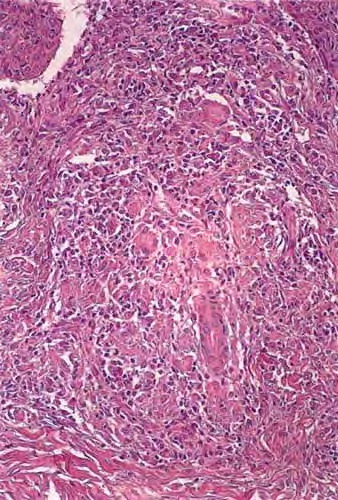

Scondary syphilis = الافرنجي الثانوي